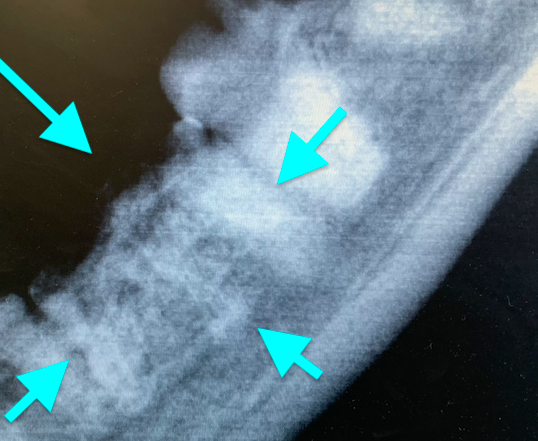

Внутриротовые рентгенограммы всей полости рта являются важным диагностическим инструментом, помогающим выявлять и классифицировать резорбцию зубов. Нередко резорбция, отмеченная на одном зубе, выявляется на таком же зубе симметрично.Существуют два широко используемых метода классификации резорбции зубов у кошек на основании радиографической картины (по стадии и типам). Рентгенологическая картина резорбции зуба варьируется от незначительных рентгенопрозрачных дефектов поверхности зуба в области цементно-эмалевой границы до обширной резорбции замещающего корня, придающей зубу пятнистый или изъеденный молью вид. Планирование лечения также включает рентгенографическую оценку пространства периодонтальной связки.

Классификация по типам рентгенологических проявлений резорбции зубов1 (фото 17):

Тип 1: наблюдается потеря альвеолярной кости, примыкающей к области резорбции зуба, на других участках зуба сохраняется нормальное пространство периодонтальной связки.

Тип 2: потеря пространства периодонтальной связки и цемента зуба из-за сращения корня зуба с альвеолярной костью (дентоальвеолярный анкилоз), резорбирующаяся структура зуба выглядит менее рентгеноконтрастно, чем неповрежденный зуб.

Тип 3: комбинация типов 1 и 2.